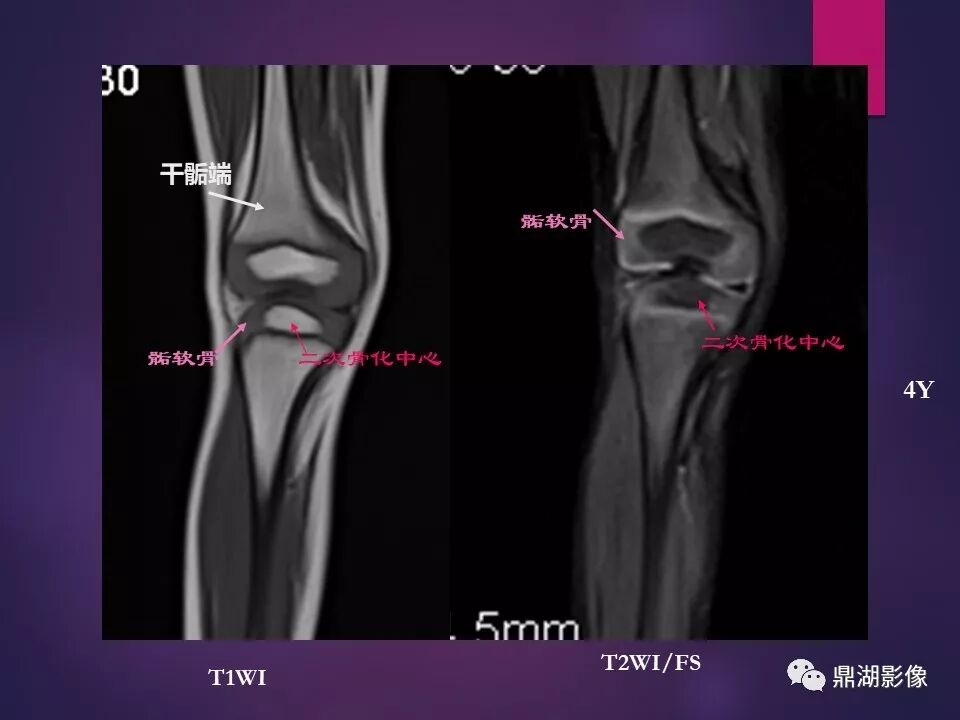

来源于:鼎湖影像 贵阳医学院医学影像系